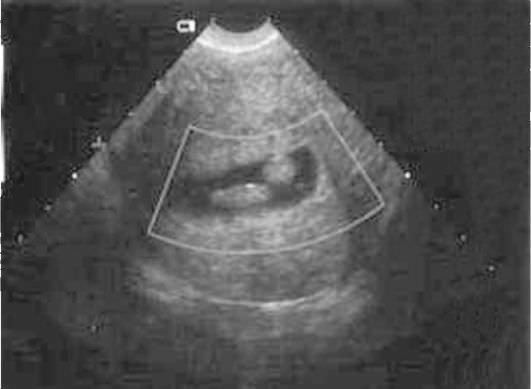

На основании чего доктор ставит диагноз? Специалист знает, как он выглядит на снимке. Ниже приведено фото, на котором изображен полип.

Конечно, заключение должен делать не сонолог, а опытный гинеколог. Сонолог лишь указывает подозрительные моменты на снимках и ставит предварительный диагноз. Врач оценит эхогенность органов. На что он обратит внимание?